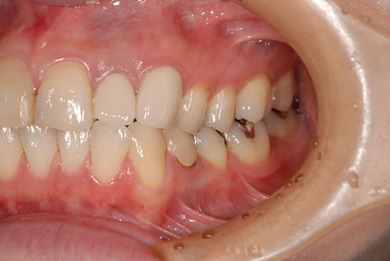

治療内容 オールセラミッククラウン2本(オールセラミック用の土台2本)

治療後

• 治療後